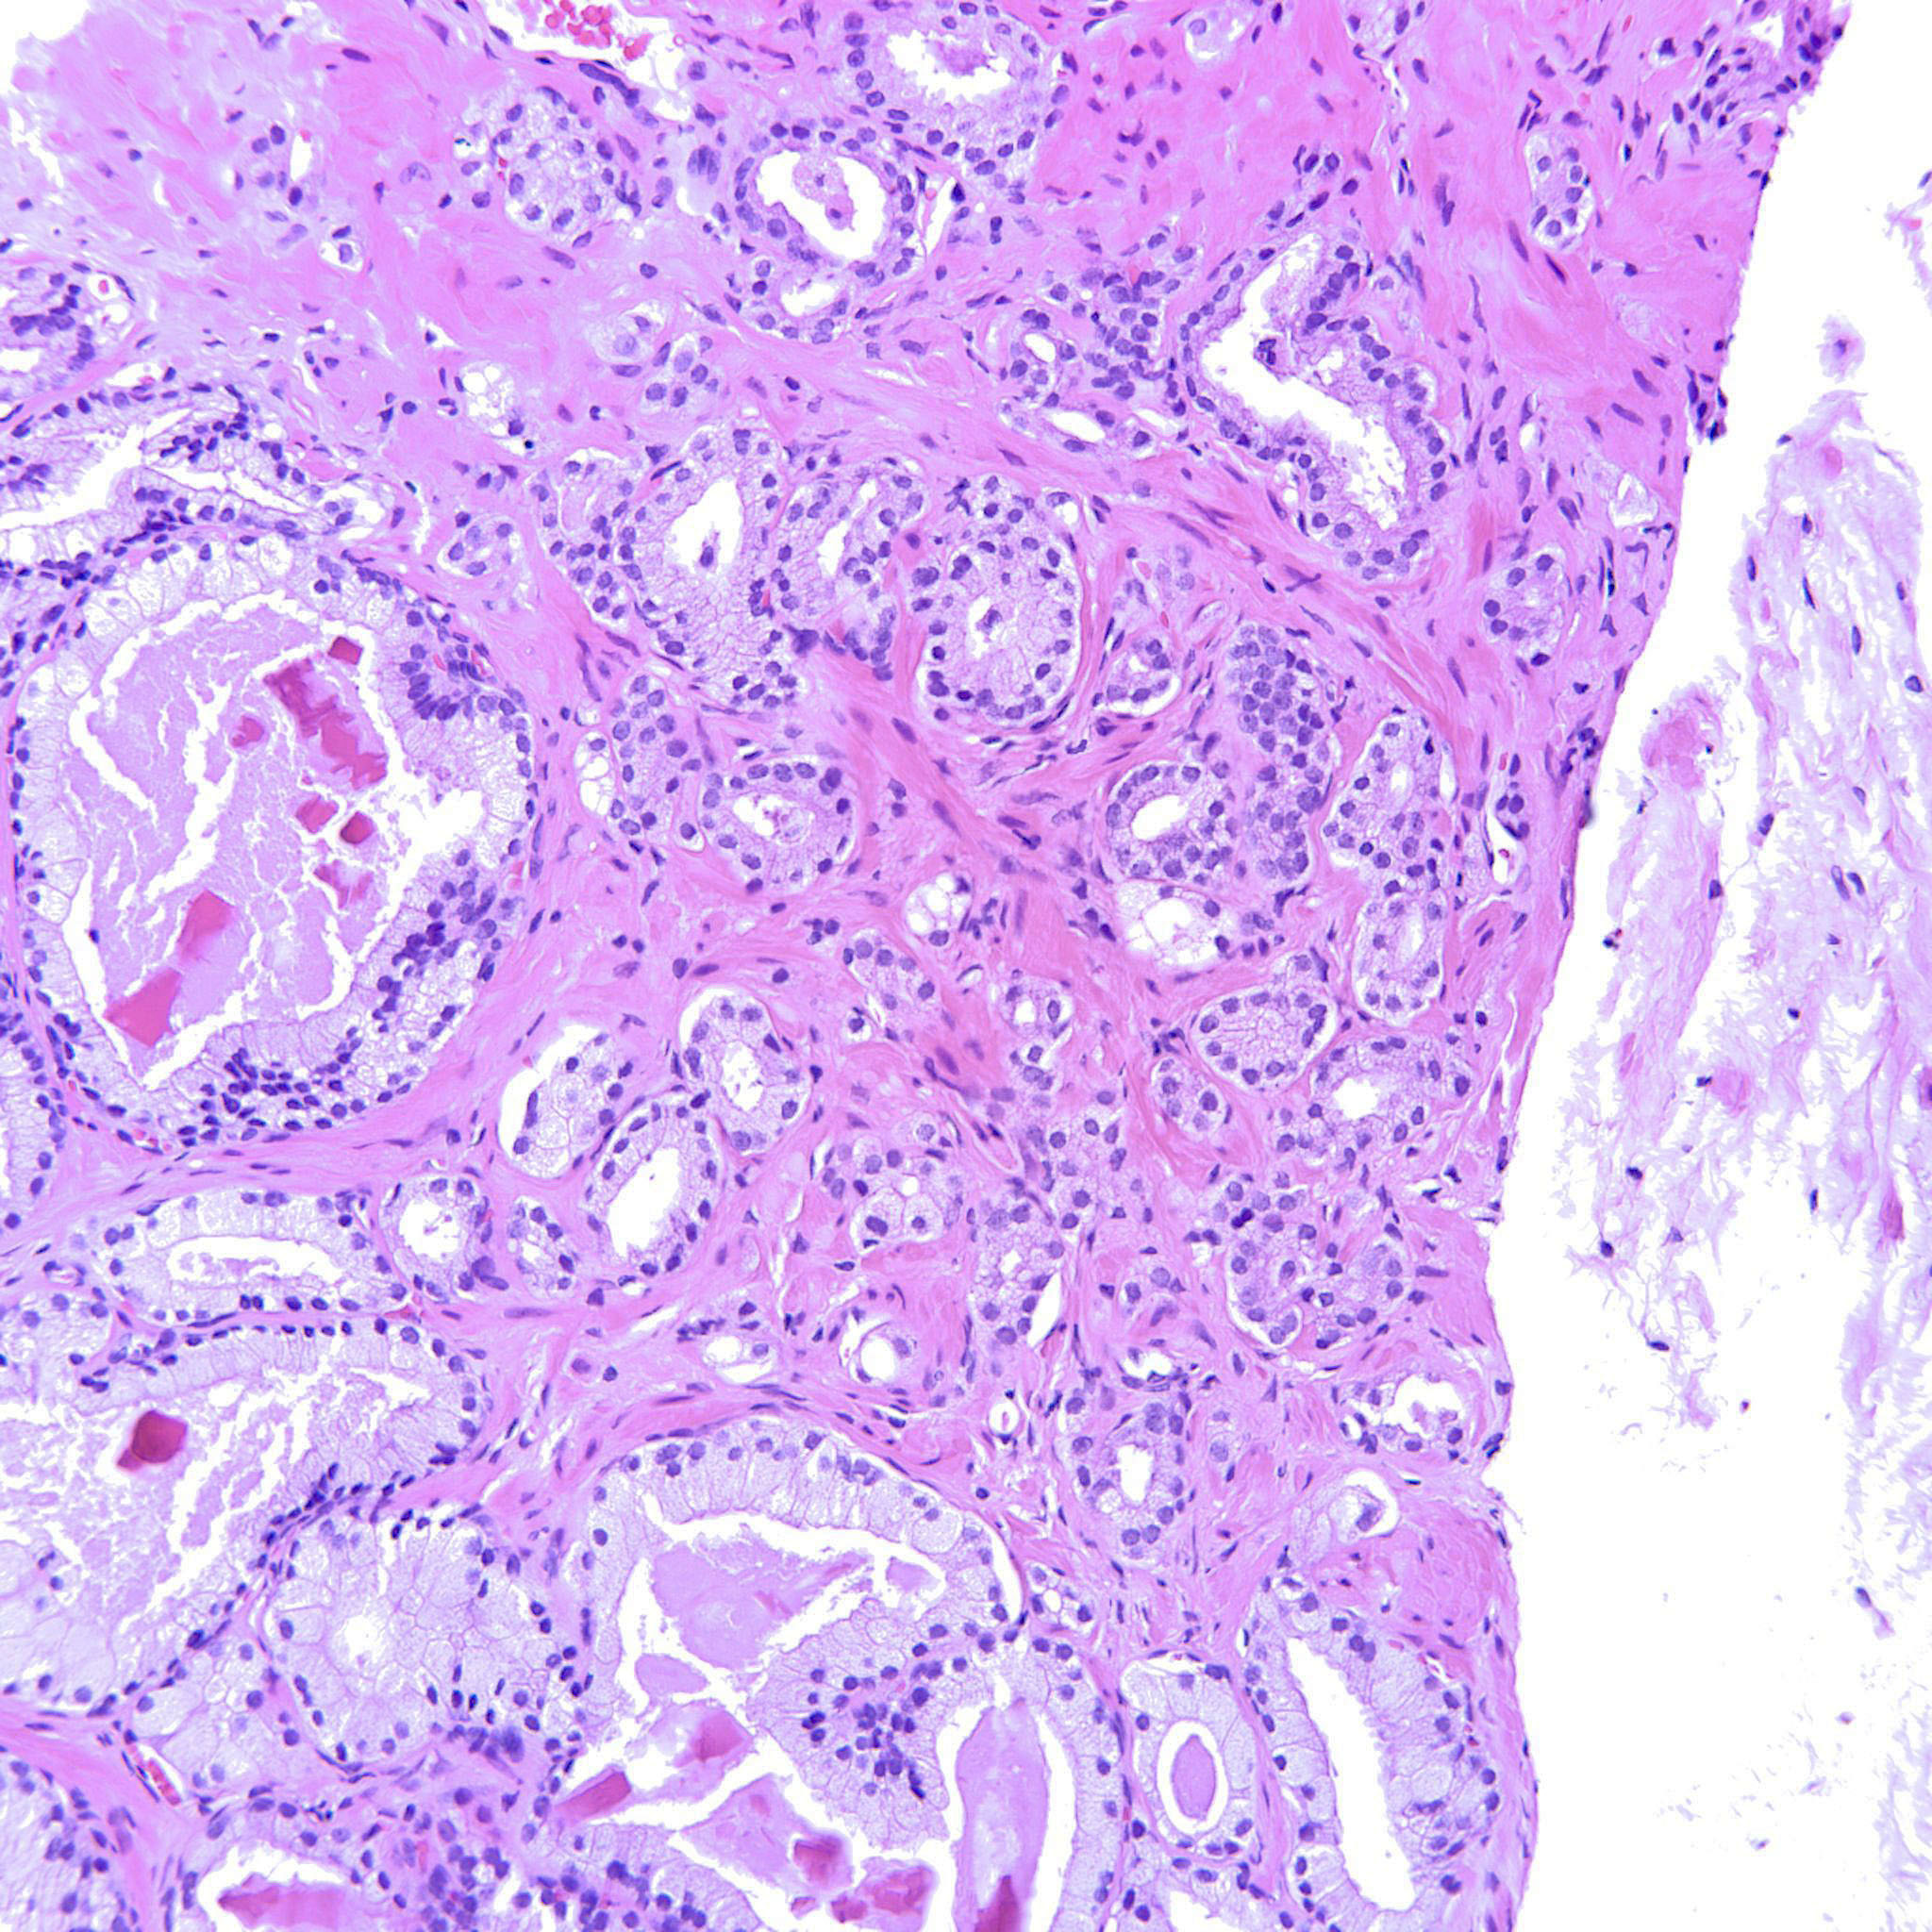

Consensus grade: GS 3+4=7 (ISUP 2)

| Pathologist 1 | GS 3+4=7 (ISUP 2) | Borderline lower |

enough poorly formed glands |

The issue here is threshold for the number of poorly formed acini required to call pattern 4. I would need to see at least 3 levels to be most confident in assigning a grade |

Poorly formed glands. "Single cells" interpreted as tangential sectioning. |

Most of the tumor is GP3 but there are also some poorly formed glands.